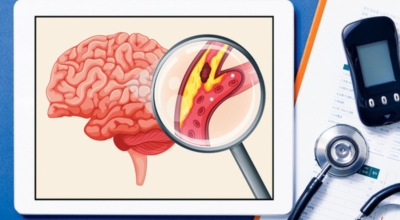

뇌졸중은 뇌경색과 뇌출혈 두가지로 나뉘게 돼요. 먼저 뇌경색은 뇌혈관이 막혀 영양분과 산소를 제공하는 피가 통하지 않는 상태로 원은은 크게 세 가지로 나눌 수 있는데요 동맥경화증이 생겨 좁아진 부위로 인하여 혈액공급이 부족해지거나 좁아지다가 결국 막혀버리는 경우, 큰 혈관에서 분지한 작은 혈관들이 고혈압 등으로 압박을 받으면 혈관이 막히는 경우가 있어요.

또한 심장 판막질환이나 심방세동 또는 심근병 등과 같은 심장 질환이 있는 경우 심장에서 혈전이 만들어지고 그게 뇌로 흘러가게 되면 뇌혈관을 막게 되는 경우가 있어요. 뇌출혈은 뇌경색과 반대로 뇌혈관이 터져서 생기는 뇌내 출혈과 거미막하 출혈로 나누게 돼요. 거미막하출혈은 혈관벽의 약한 부분이 부풀어 오르는 뇌동맥류가 터지는 경우와 관련성이 크다고 해요.